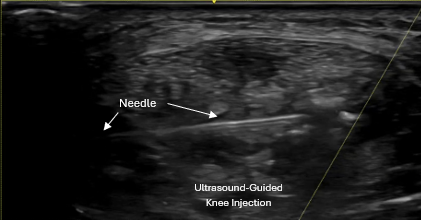

Ultrasound-guided knee injection precisely targeting tendon and joint pathology

Ultrasound also allows for same-day ultrasound-guided treatment when appropriate.

All injections are performed using real-time ultrasound guidance to ensure precise placement into the area of pathology